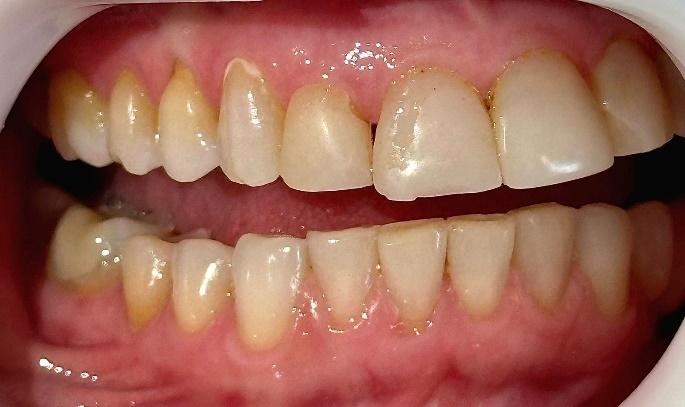

A coleta de dados foi iniciada com a realização de uma consulta inicial, na qual foi conduzida uma anamnese detalhada para levantamento do histórico médico e odontológico do paciente, bem como de suas principais queixas e expectativas em relação ao tratamento estético proposto. Em seguida, foi realizado um exame clínico minucioso com o objetivo de avaliar as facetas previamente instaladas, observando critérios como adaptação marginal, integridade do material restaurador e condições periodontais adjacentes. A saúde bucal geral do paciente também foi analisada nesta etapa, no aspecto inicial foi observado o acúmulo de biofilme causado pela má adaptação cervical, retração gengival, trincas e fraturas derivadas da oclusão desbalanceada, conforme apresenta a figura 1,2,3 e 4.

Figura 1: Vista do lado superior direito.